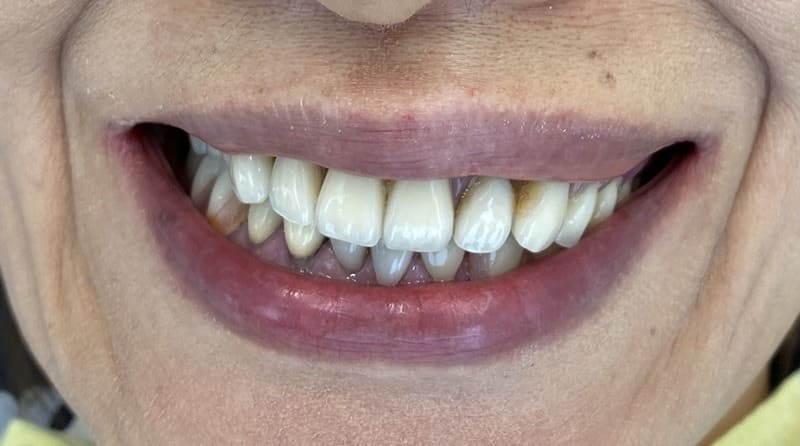

スマイル時の口元

Before

After